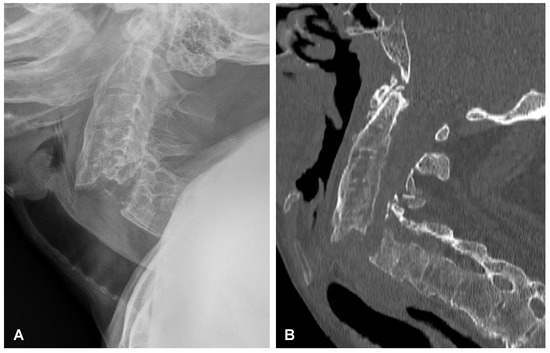

2.4. Surgery of the Cervical Spine Due to the Tetraparesis

Following the initial diagnostics, the patient was transferred to the operating room. The combined anterior and posterior osteosynthesis (360° fixation) at the C4-C5-C6-C7 levels were performed. In the first stage of surgery, the anterior stabilization plate (50 mm) and locking screws (Zephir; Medtronic, Minneapolis, MN, USA) under intraoperative 2-D fluoroscopy control were placed. In the second stage of surgery, the patient was turned and posterior-stabilized (Ellipse; Globus Medical, Audubon, PA, USA) with lateral mass screws (8 mm × 14 mm) using free-hand technique based on anatomical landmarks due to poor intraoperative visualization of cervicothoracic region capabilities using 2-D fluoroscopy was performed. A control CT scan performed one day after the operation revealed the correct placement of all the implants (Figure 9). After surgery, the patient remained in deep tetraparesis with minimal movements in the lower limbs but no movement in the upper limbs. Early postoperative rehabilitation at the bedside was initiated. However, the patient remained prolonged endotracheally intubated but was conscious and awake due to the retention of airway secretions, as well as was parenterally fed for 5 days. The patient was empirically administered intravenously with amoxicillin with clavulanic acid (1 g/0.2 g every 12 h). After successful extubation, the tracheostomy and percutaneous endoscopic gastrostomy (PEG) were not performed. After 12 days, the patient was discharged with no signs of infection and transferred to the rehabilitation center.

Figure 9. Postoperative sagittal CT scans (non-contrast enhanced) after the two-stage surgery of the cervical spine demonstrating placement of the anterior plate with locking screws (A) and posterior lateral mass screws (B) at the C4-C5-C6-C7 levels.